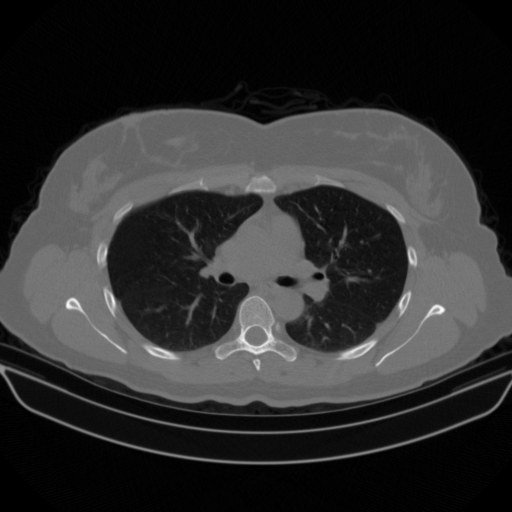

Image Grid

4Γ—3 grid: Rows show different image types (Original NATIVE, Reconstructed NATIVE, Original VENOUS, Generated VENOUS), Columns show windowing techniques (No Window, Lung Window, Mediastinum Window)

Lung window (WL -600, WW 1500 β†’ Low βˆ’1350, High +150)